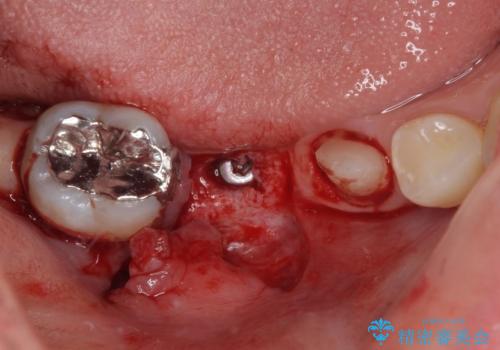

- インレーブリッジをインプラントにやり替えて銀歯を白くしたいとのことで来院された患者様です。

既に抜歯をして歯のない箇所にはインプラント治療をし、ブリッジの土台となっている歯のうち、手前側の小臼歯は既に根管治療をされている歯なのでオールセラミッククラウンへのやり替え、奥側の大臼歯はセラミックインレーへのやり替えをしていくこととしました。

根管治療のやり直しは希望されなかったため、土台の部分からのやり替えです。